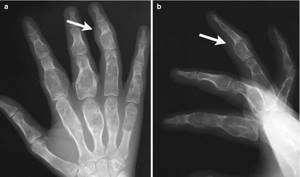

Мелореостоз или «болезнь Лери» — это резкое уплотнение костной ткани (остеосклероз), которое вызывает избыточный рост костей, их деформацию и связанные с этими факторами боли. Заболевание является врожденным. На рентгеновских снимках пораженные мелореостозом кости выглядят, как свечи с которых оплывает воск.

Признаки и симптомы мелореостоза включают в себя: неправильное развитие костей, в том числе корковое утолщение (на рентгене проявляется в виде «стекающих капель воска с свечи»), конечности разной длины, опухание суставов, аномалии мягких тканей, отсутствие или аномалии некоторых мышц, подкожные кальцификации и контрактуры. В результате таких нарушений, у человека происходит иммобилизация суставов, ограничение в диапазонах движений, боль и жесткость, отек конечностей и сосудистые нарушения. Реже, человек может развить тяжелые поражения костей, которые могут сжимать окружающие нервы.

Диагноз можно точно поставить только с помощью рентгена. На нем видны участки, на которых кость сильно уплотнена. К тому же характерна форма таких образований – «стекающая».

Чаще поражаются короткие и длинные, а также мелкие кости руки и ноги. Иногда затрагиваются лопатки или кости таза. Уплотнение обычно не затрагивает всю кость, а только отдельные ее участки.